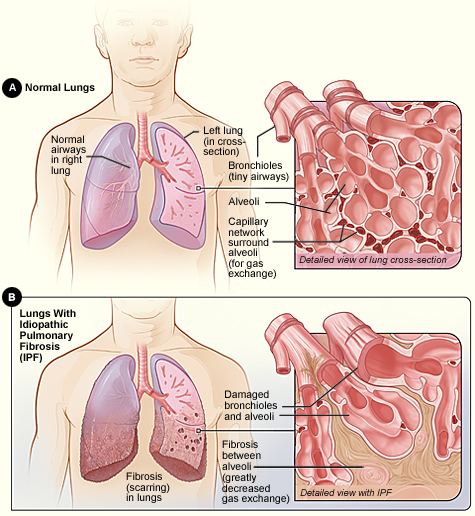

3. Pulmonary Fibrosis:

This is a result of inelasticity of the fibrous connective tissues that build up in the lungs.

3. Pulmonary Fibrosis:

This is a result of inelasticity of the fibrous connective tissues that build up in the lungs.